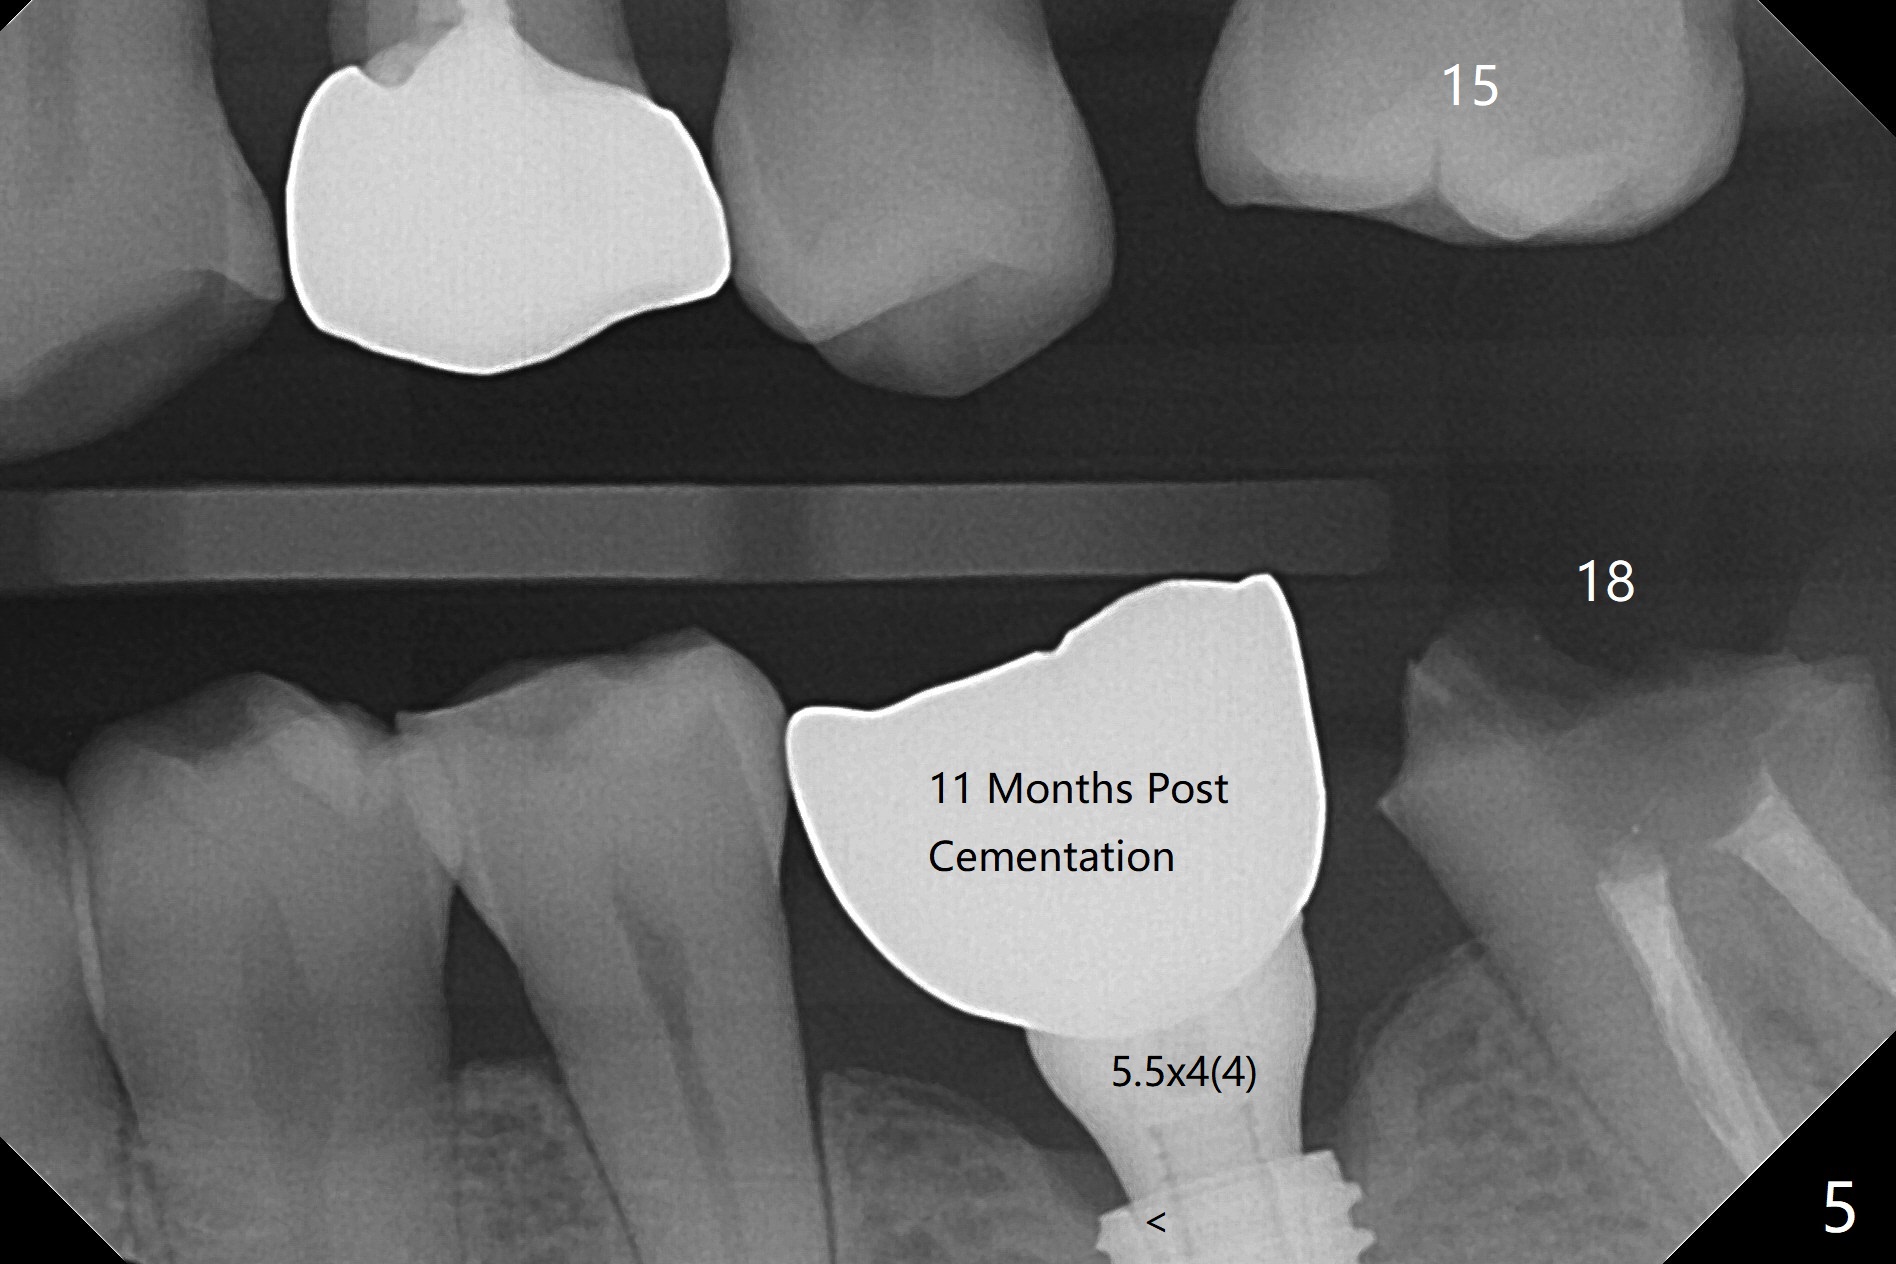

With one carpule of Xylocaine (34 mg with 17 mcg of Epinephrine), a 5x8.5 mm implant is placed at #19 in a timely and painless manner. The patient is pleased as compared to her previous implant placement at #3 and 30. Due to the thin buccal bone, the implant is placed ~.5 mm deeper than designed; a 6.5x4(2) mm healing abutment is incompletely seated (Fig.1). A smaller and skinny one (5.5x7(4) mm) is seated normally (Fig.2). Regional panoramic X-ray shows clearance from the Inferior Alveolar Canal (Fig.3 *). Although there is crestal bone resorption 6 months postop, the bone density next to the 1st thread is high (Fig.4 >). A 5.5x4(4) mm cemented abutment is placed for impression. The patient returns with #18 crown dislodgement and #19 crown loosening 11 months post cementation (Fig.5 <: gap between implant and abutment). Since the crown and abutment are unable to be torqued properly, they are removed (Fig.6). A narrower abutment is able to be seated apparently completely while a metal post (Fig.7 *) is tried in in the distal root of #18. To reduce the chance of re-fracture of #18 crown, the tooth #15 needs to be distalized orthodontically so that an implant will be placed at #14 (Fig.5).